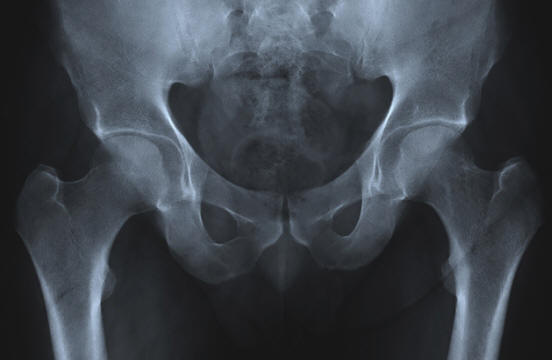

Super husté kosti

Stárnutí je nevyhnutelně spojeno s výskytem hmoty problémy. Běžným příkladem je osteoporóza, úbytek kostní hmoty a hustota. To vede k nevyhnutelným zlomeninám kostí, zlomeným boky a vystupující hrby. Skupina lidí však vlastní jedinečný gen, ve kterém je skryto tajemství léčby osteoporózy.

Tento gen byl nalezen v populaci afrikánů (Jihoafričanů s Nizozemský původ). Vede to ke skutečnosti, že lidé zvyšují kostní hmotu po celý život a ne ztratit ji. Konkrétně se jedná o mutaci v genu SOST, která řídí protein (sklerostin), který reguluje růst kostí.

Pokud Afrikaner zdědí dvě kopie mutantního genu, dostane porucha sklerózy, která vede k proliferaci kostí tkáň, gigantismus, paréza obličeje, hluchota a časná smrt. To je jasné že tato porucha je horší než osteoporóza. Ale pokud Afrikaner zdědí jen jedna kopie genu, jen dostane husté kosti pro celek život

Ačkoli v současné době jsou využívány výhody tohoto genu pouze její heterozygotní nositelé, vědci studují DNA Afrikaners doufat, že najde způsoby, jak zvrátit osteoporózu a další kostní poruchy. Na základě již získaných znalostí vědci zahájili klinická hodnocení inhibitoru sklerostinu, který je schopen stimulovat tvorbu kostí.